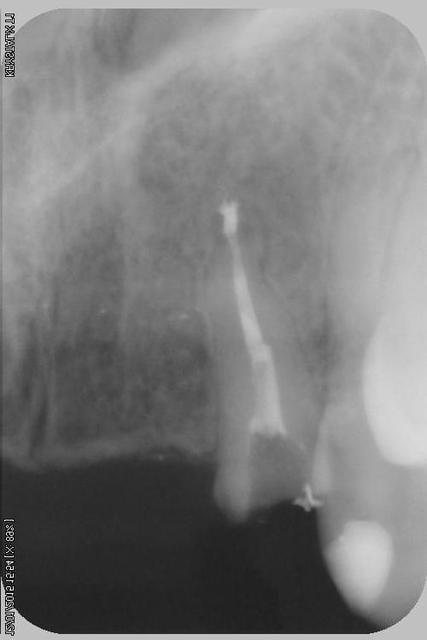

Donc dans un premier temps,je décide d'essayer de retraiter 12/22, de toute façons ça ne peut pas être pire que ce qui tiens depuis 10 ans... enfin 12 mobilité quasiment 3.

ensuite Srew post (bouh...) et résine, afin de pouvoir poser un provisoire et réfléchir à l'avenir du parodonte...car il va y avoir un problème quelle que soit la solution choisie.

Sur la reprise de 22 je pense que tu as fais un beau "tout-droit" à l'apex... le canal devait suivre la courbure.

Tu es bon pour faire une chir-apicale dans quelques mois !

je pense que le tout droit existait déjà..

oup's j'ai omis la digue...

Chir apicale si on garde la dent...

Oui oui, c'est certain ! il y avait au moins une belle butée bien engagée. Ce qui expliquerai que l'ancien traitement n'allait pas jusqu'à l'apex.

Et avec les instruments de rotation continue agressifs de reprise d'endo que l'on a maintenant, on s'engage dans la butée et on la "termine"... ça m'arrive aussi de temps en temps... de toutes façons, repasser de vieilles butées comme ça, même les endos exclusifs n'y arrivent presque jamais et font une chir apicale d'emblée.